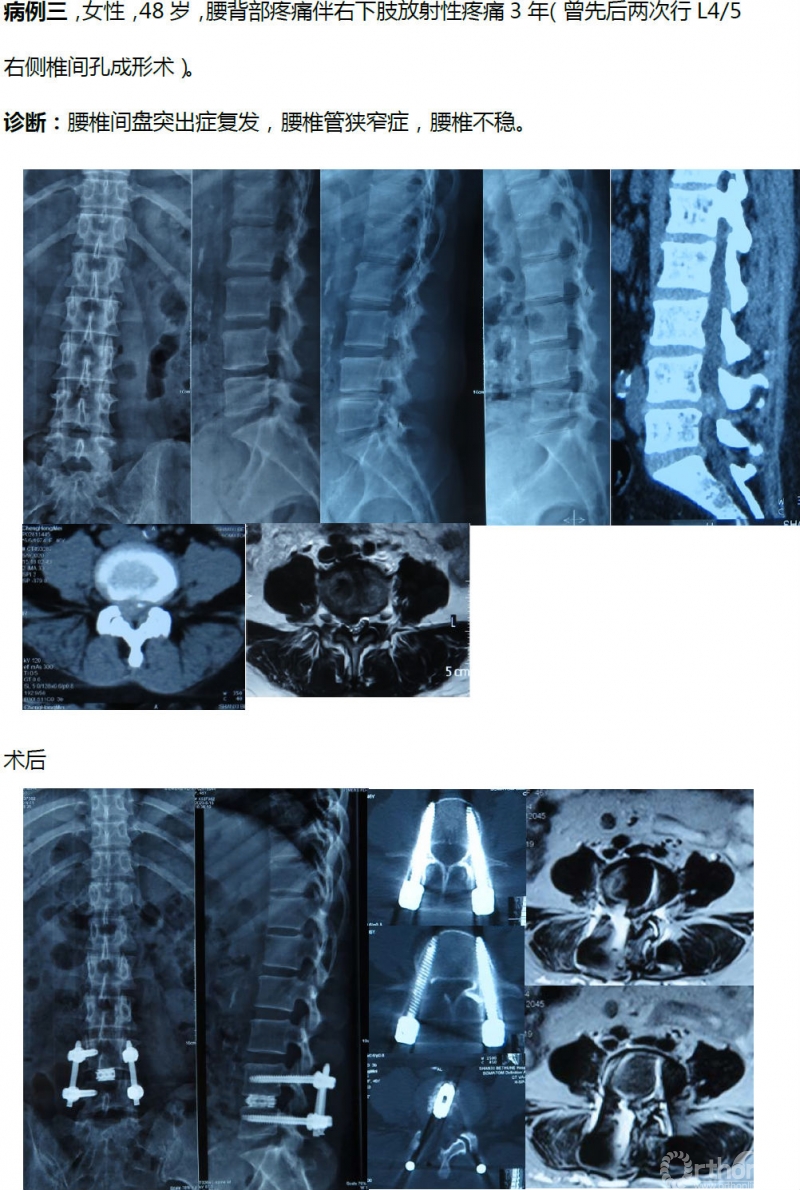

病例分享:(滑动查看)